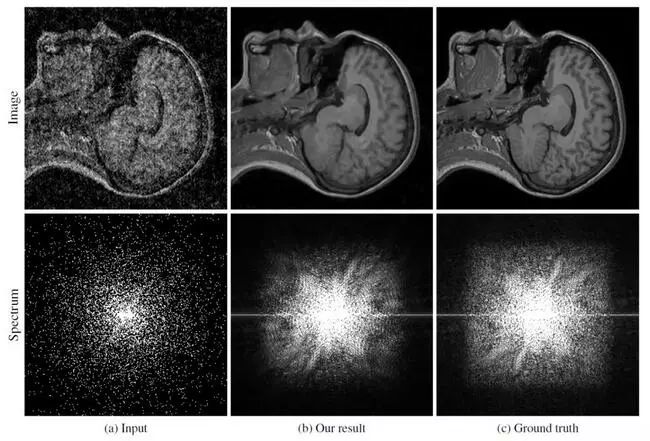

而且除了我们日常生活中拍摄的照片,这个AI还能用于增强已知的含有大量噪点的图像,比如天文摄影、核磁共振成像(MRI)或大脑扫描图像。

研究人员利用XMX数据集中约5千张MRI图像训练了AI的去噪能力,他们将原始清晰图像添加了不同比例的噪点,只用它们训练AI,也就是说AI并不知道清晰的MRI图像是怎样的,完全靠自己的学习将图像复原。

我们可以看到,AI去噪后的图像清晰度已经非常接近原始图像。